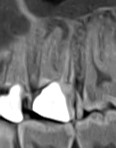

- Consultație și diagnostic precis (radiografie digitală sau tomografie CBCT)

- Utilizarea microscopului endodontic pentru vizibilitate maximă